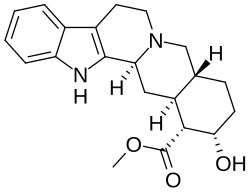

Beta-1 blocker

Since beta-1 receptors are mainly located in the heart, most beta-1 blockers take abnormalities associated with the heart as the target.[5] It treats medical conditions like hypertension, arrhythmias, heart failure, chest pain, and myocardial infarction. It treats other symptoms unrelated to heart like migraines and anxiety.[5]

Beta-1 blocker

Beta-1 blocker will stop the action of beta-1 receptor via occupying the beta-1 receptor without any activation.[5] The beta-1 receptor is a G-protein-coupled receptor with Gs alpha subunit as its main communication method.[5] By signaling Gs, adenylyl cyclase is recruited to activate a cAMP pathway, which potentiates the receptor.[5] This kind of receptor is located at the heart, kidney and adipose tissue.[5] Eventually, a higher cardiac output(or an increased amount of perfusion to organs) will be resulted.[5] Moreover, more renin is released from the kidney to produce more angiotensin II, increasing the blood volume.[5] Moreover, it encourages lipolysis in adipose tissue. Beta-1 blocker blocks the beta-1 receptor and stops the action mentioned above. (signaling Gs, thus activate cAMP pathway by recruiting adenylyl cyclase, leading to higher cardiac output, renin release and lipolysis)